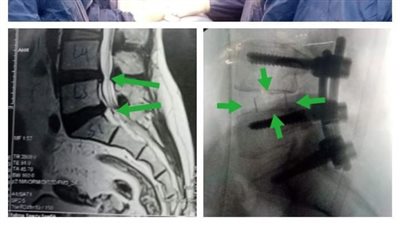

نجاح أول جراحة لإصلاح اعوجاج بالعمود الفقرى بمستشفى تمى الأمديد

فريق جراحى بكفر شكر التخصصى ينقذ مريضة من الإصابة بالشلل بعد تركيب قفص كربوني